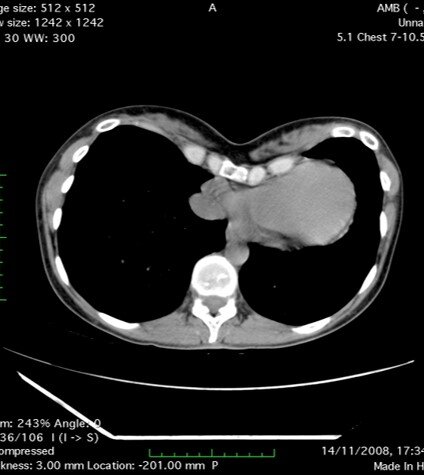

Основным опасением в данном случае служит предположение, что с расширением грудной клетки у беременных может произойти смещение пластины, усиление болей вследствие избыточного давления пластины на подлежащие ткани. В литературе встречаются отдельные публикации, исследующие данные вопросы (1. Should the pectus bar be removed before pregnancy? Two case reports. Chang PK et all. Thorac Cardiovasc Surg. 2011 Feb; 59(1):54-6. 2. Successful Singleton and Twin Pregnancies with the Nuss Bars in Place. Jaroszewski DE et all. Ann Thorac Surg. 2015 Nov; 100(5):1877-8).

Исследователи указывают на, действительно, появление болей в области пластин в третьем триместре беременности, однако без какого либо значимого их смещения. В остальном беременности протекали без осложнений и разрешились без негативных последствий для матери и ребенка самостоятельно или путем кесарева сечения. Все авторы отмечают недостаточную изученность данной проблемы и необходимость проведения дальнейших исследований.